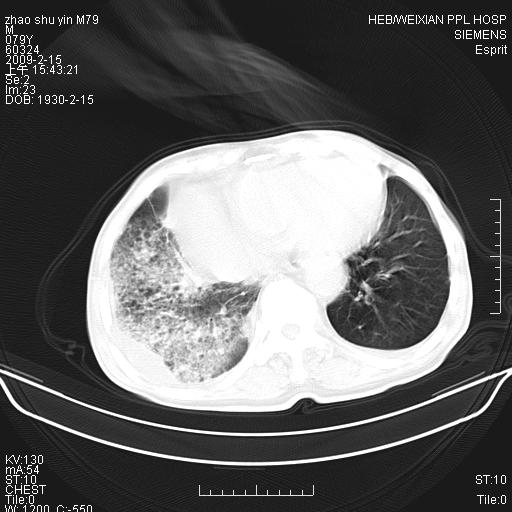

标题: CT18303:M79Y,右下肺病变

主因高热、寒战4天,伴有咳嗽,腹痛。

1。右下肺磨玻璃及蜂窝影考虑炎症 建议抗炎治疗后复查

2。右侧胸膜增厚 、右侧包裹性积液

3。心影增大 ,左心房增大为甚

4。右下肺门饱满(肿大淋巴结)

右下肺蜂窝影加右下肺门淋巴结肿大,要考虑肺泡癌。

我考虑:1、右下肺肺泡癌并感染,肺门淋巴结转移可能性大。2、右侧胸腔积液。